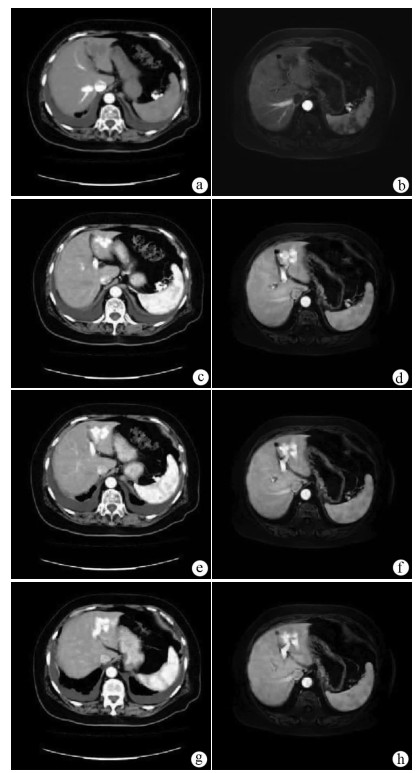

A case of congenital intrahepatic portosystemic venous shunt with hepatic encephalopathy in the elderly

Figures(3)